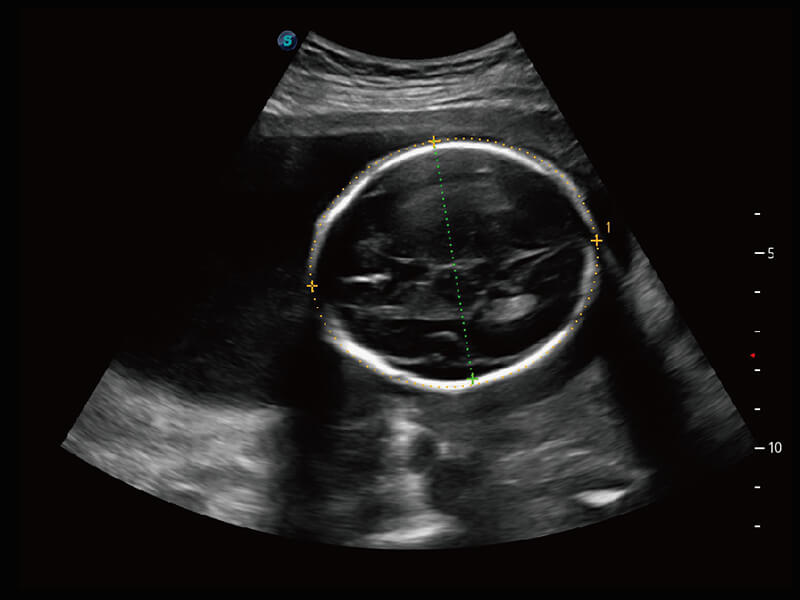

超宽频带技术,为容积成像带来优质的二维图像基础,为您呈现丰富的结构细节,栩栩如生地展示宝宝的宫内形态以及各种组织的立体结构。